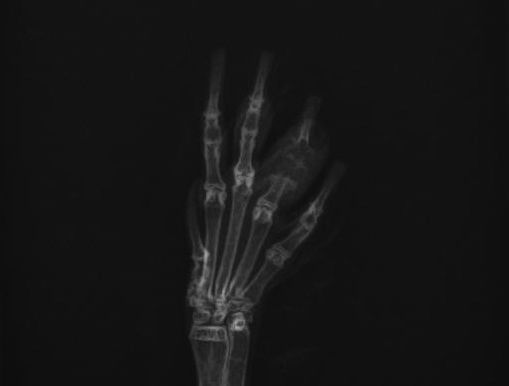

Rabbit Toe Amputation & Osteomyelitis Species: Rabbit (Age 10) Location: Queens, NY Rabbit Osteomyelitis and Thymoma Management for Queens Patient at Long Island Bird & Exotics Veterinary Clinic Geriatric rabbits, specifically those over the age of 8, often face complex health challenges that require a delicate balance of surgical intervention and long-term medical management. Recently, we treated a distinguished 10-year-old rabbit from Queens, NY , proving that age is just